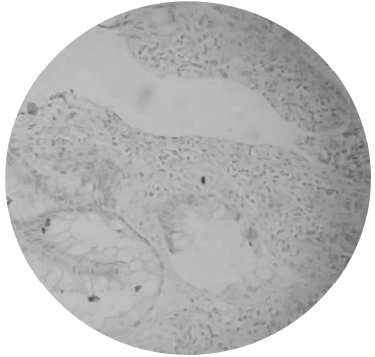

Paciente de 37 anos, transplantado renal por diabetes tipo 1 há 5 anos, vai a consulta ambulatorial com quadro de diarreia aquosa, mais de 10 evacuações ao dia, sem sangue ou muco e febre baixa há 2 meses. Encontra-se em uso de micofenolato mofetil 1 g/dia, tacrolimus 3 mg/dia e prednisona 5 mg/dia. Ao exame físico, encontra-se hidratado e abdômen inocente. Realizou colonoscopia que não evidenciou alterações macroscópicas, porém o resultado de imunohistoquímica em anatomopatológico evidenciou o que é mostrado na figura abaixo.

A causa provável da diarreia é